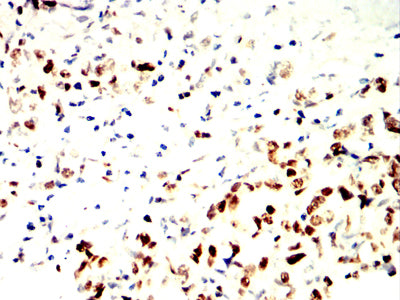

分类: 科研抗体货号: 32376别名: hN2; AGS2; HJCYS应用: IHC,IF,FCM反应种属: Human

-